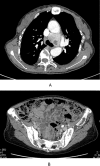

Case presentations: A 46-year-old female with chief complaints of bone pain and gait disturbance was referred to our hospital. Physical examination revealed many mobile teeth in her oral cavity, distortion of the vertebral body, and bowlegs. Laboratory tests showed hypercalcemia, hypophosphatemia, and elevated serum levels of intact parathyroid hormone. Chest CT revealed a 42-mm well-defined, enhancing mass in front of the left-sided tracheal bifurcation. Her findings were diagnosed as primary hyperparathyroidism due to an ectopic mediastinal parathyroid tumor. We performed a median sternotomy and resected the tumor. The tumor was a solid, yellowish-brown mass measuring 42×42 mm. Pathologically, the tumor consisted mainly of chief cells with some oxyphil cells; there were no necrotic areas or nuclear atypia, and few mitotic figures. We diagnosed the tumor as an ectopic mediastinal parathyroid adenoma. Eight months after the resection, her serum calcium, phosphorus, and intact PTH levels were normal.